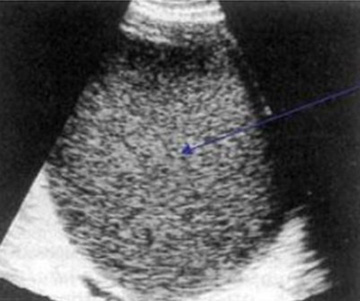

- трансвагинальное и / или трансабдоминальное УЗИ (позволяет увидеть новообразование в реальном времени, определить его размер, локализацию, плотность структуры, структуру и содержимое);